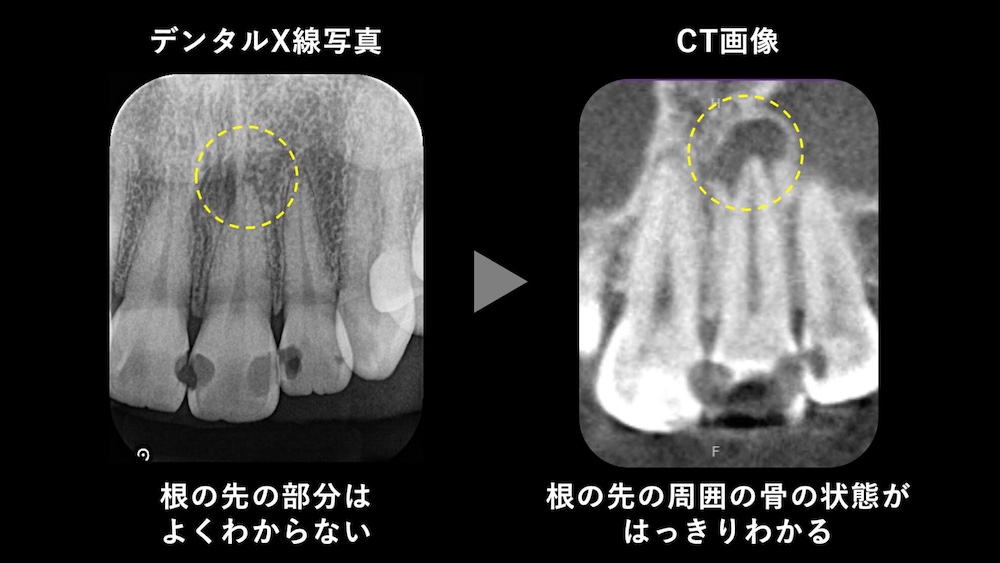

レントゲンは、硬組織(歯や骨などの硬い組織)を移す検査であるため、歯の神経自体は写りません。しかし、根の先に病変・骨の吸収の有無をみることで、間接的に歯の神経の状態を推測することができます。

通常、歯は全周を骨に覆われていますが、歯の神経が壊死し、根の先に根尖性歯周炎という膿が生じると、歯の周りの骨に黒い影が認められるようになります。つまり、「根の先の骨が吸収している=歯の神経はおそらく死んでしまっている」と判断できるといえます。

また、通常のレントゲンだけでは、骨の状態を詳しくみることはできません。根の先の骨の吸収があるか否かで、治療が必要かどうかだけではなく、治療戦略自体も変わってきます。そのため、正しい診断のためには、通常のレントゲン写真に加え、CTによる三次元的な画像評価も必須であるといえます。